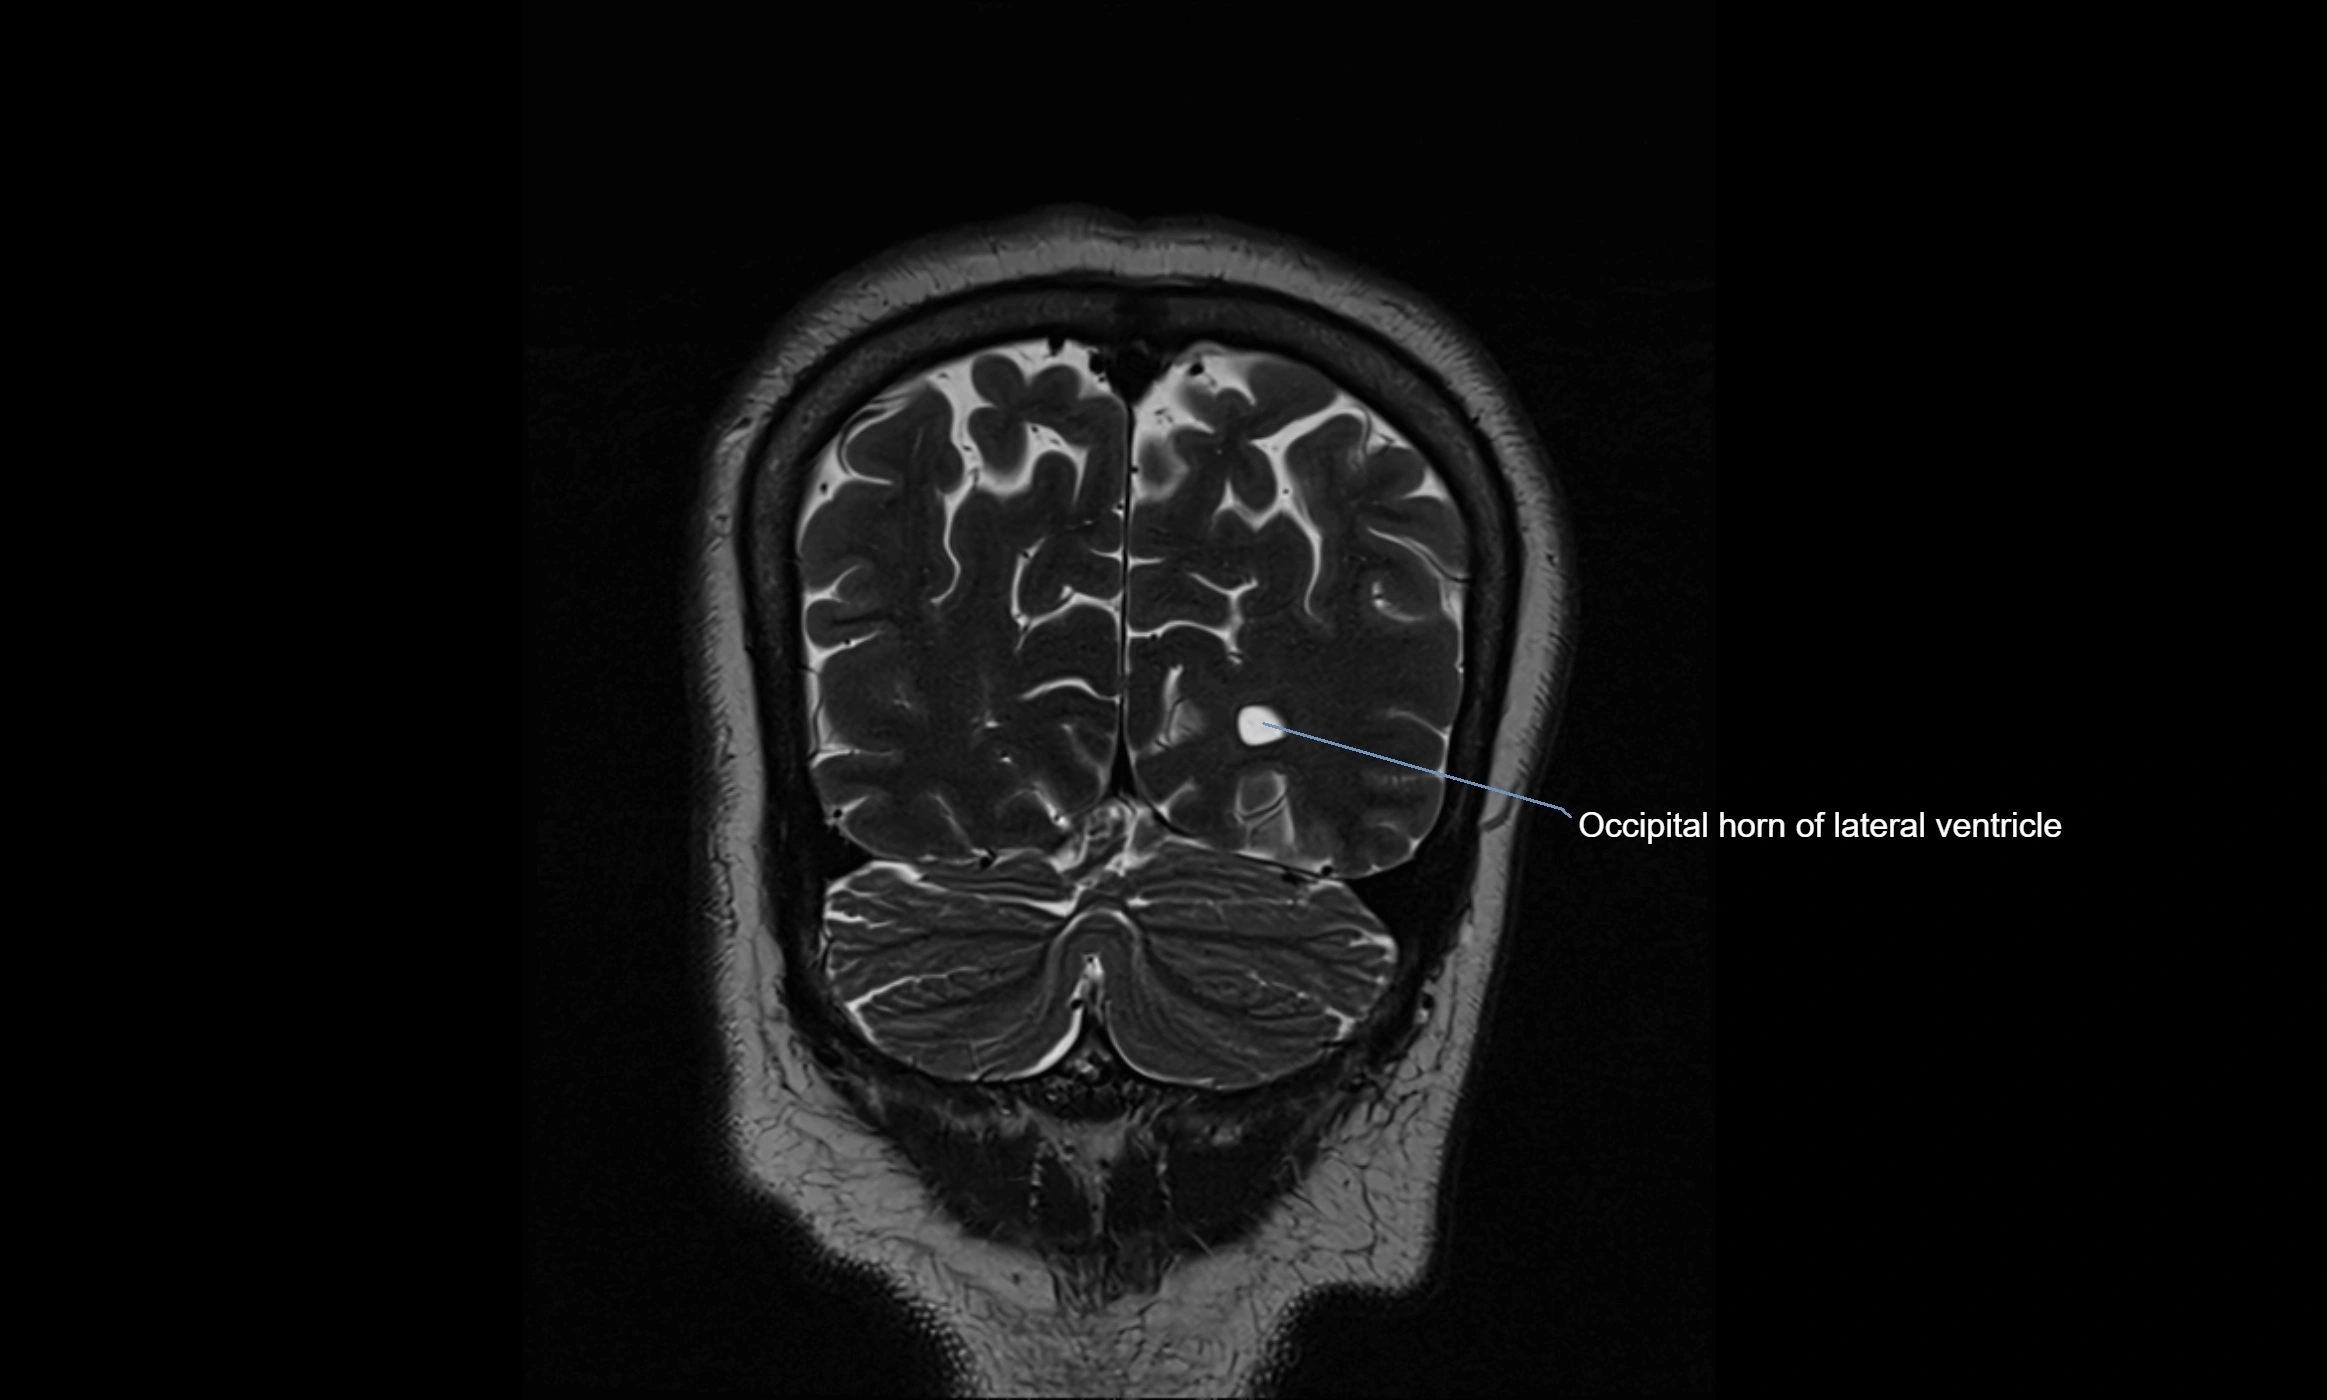

MRI images

image